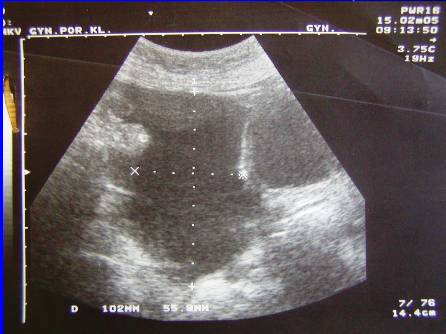

2.Recidiva (generalizace do dutiny břišní, st.p.HY a AE) pac.J.U,tu markery, punkce ascitu, cytologie

Recidiva (generalizace do dutiny břišní, st.p.HY a AE), tu markery, pac.J.U, punkce ascitu, cytologie.